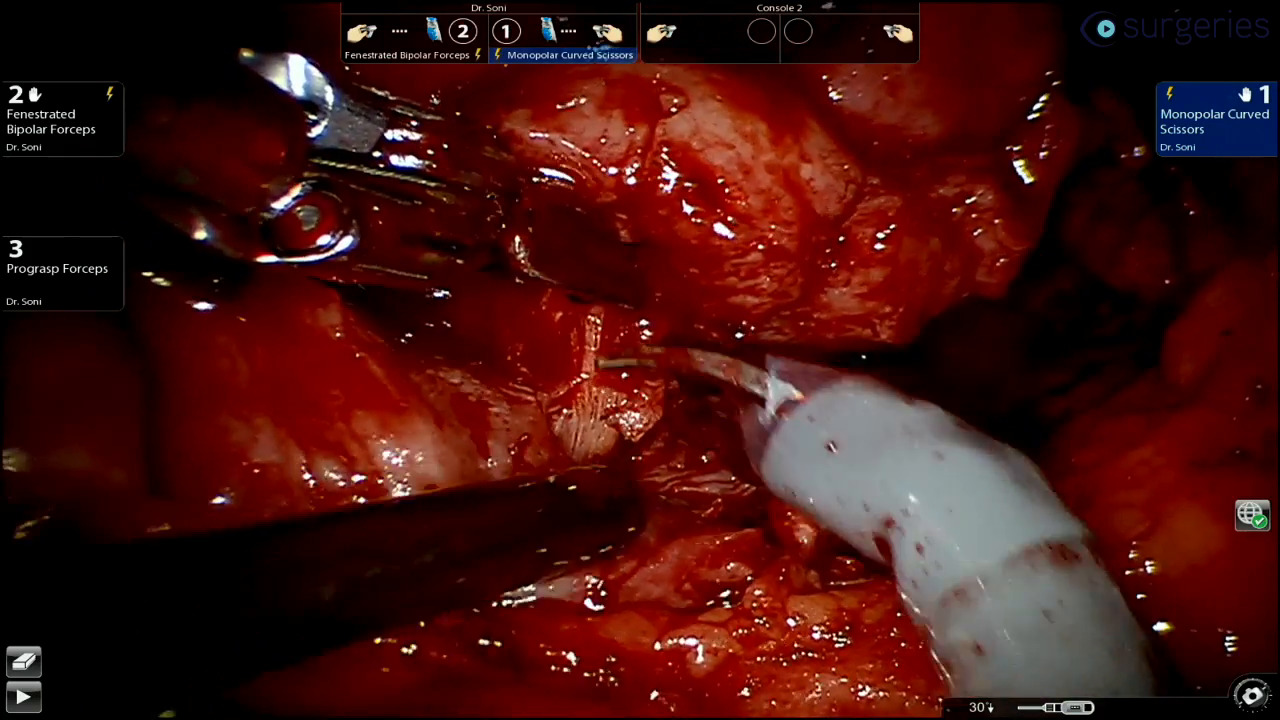

Watch the Full VideoIntroduction Neck dissection stands as a crucial surgical procedure predominantly utilized in addressing head and neck cancers. It involves the methodical elimination of lymph nodes and potentially adjacent tissues to curb cancer dissemination. This procedure can be delineated into several types based on the extent of surgery and the structures targeted, including radical neck dissection (RND), modified radical neck dissection (MRND), selective neck dissection (SND), and extended neck dissection.[1] Neck dissection is recommended for various conditions such as metastatic neck cancer, cancers affecting the oral cavity, pharynx, larynx, or thyroid with a high risk of lymphatic spread, and as a prophylactic measure in cases of head and neck cancers with a high risk of occult metastasis.[1] Understanding the anatomy of the cervical lymphatic system, which is divided into distinct levels (I-VII) each containing specific groups of lymph nodes, is essential for conducting effective neck dissection.[2,3] The radical neck dissection (RND), introduced by George Crile Sr. in 1906, was long regarded as the standard treatment for metastatic neck disease.[2,4] However, modifications to the procedure have been developed over time to reduce associated morbidity while ensuring oncological safety.[1] Surgical procedure The surgical procedure of neck dissection typically involves a series of steps: an incision is made along an existing neck crease, subplatysmal flaps are then elevated to expose underlying anatomical structures and lymph nodes, different groups of lymph nodes are systematically removed depending on the type of dissection, and finally, the surgical site is closed in layers with the placement of a drain.[4] Complications of neck dissection may include nerve damage resulting in shoulder dysfunction, bleeding and hematoma formation, infection and issues with wound healing, as well as the development of lymphedema.[1] Conclusion Neck dissection is a vital procedure in the management of head and neck cancers, designed to remove lymph nodes that may harbor metastatic disease. The type of neck dissection performed is tailored to the extent of disease and the need to preserve function and reduce morbidity. A thorough understanding of the anatomy and careful surgical technique are essential to optimize outcomes and minimize complications. References Harish K. Neck dissections: radical to conservative. World J Surg Oncol. 2005 Apr 18;3(1):21. doi: 10.1186/1477-7819-3-21. PMID: 15836786; PMCID: PMC1097761. Jiang, Z., Wu, C., Hu, S. et al. Research on neck dissection for oral squamous-cell carcinoma: a bibliometric analysis. Int J Oral Sci 13, 13 (2021). https://doi.org/10.1038/s41368-021-00117-5 Rigual NR, Wiseman SM. Neck dissection: current concepts and future directions. Surg Oncol Clin N Am. 2004;13(1):151-166. doi:10.1016/S1055-3207(03)00119-4 Antonio Riera March, M. (2023, November 28). Radical neck dissection. Background, History of the Procedure, Problem. https://emedicine.medscape.com/article/849895-overview?form=fpf